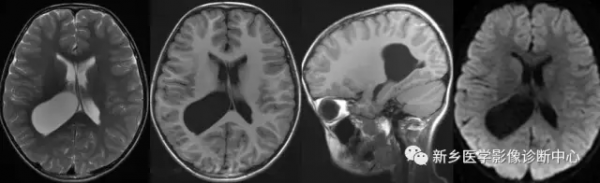

CT平掃顯示為均勻一致等或稍高於腦組織密度的腫塊,約50%出現鈣化,可見囊變,罕見出血。MRI平掃T1WI呈等或稍低訊號,T2WI一般呈等訊號,有鈣化時表現為低訊號。

增強掃描為中等度強化或明顯強化,可強化不均;邊緣光整,境界清楚。不向腦組織內侵襲,較小的腫瘤多無周圍腦水腫。腫瘤常引起側腦室顳角擴大和區域性脈絡叢鈣化移位。

氫質子波譜可見Cho峰明顯增高,缺乏NAA峰和Cr峰(腦外腫瘤),可出現Ala(丙氨酸)峰。周圍腦實質可見輕-中度水腫。瘤周水腫是由於瘤體體積較大時對腦室周圍機械性壓迫導致靜脈迴流障礙及壓力差致使水滲透出。

至腦實質所致;亦有認為是腫瘤合併區域性腦室壓力升高致室管膜水腫或腦脊液透過破裂的室管膜向白質逆流所致。兒童發現側腦室腦膜瘤應注意是否存在神經纖維瘤病可能。

特點:文獻報道側腦室三角區腦膜瘤增強掃描與脈絡叢關係密切,這是重要特徵之一,類似與腦膜尾徵,或可稱之為“脈絡叢尾徵”。